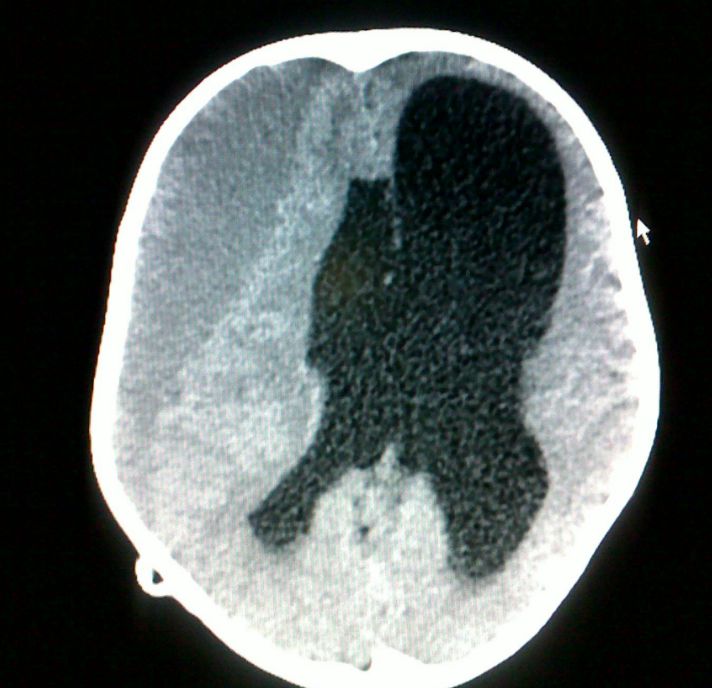

患儿VP分流术后6月,美敦立分流管调整压力致1.0,造成硬膜下积液(图3)。在患儿无明显症状前提下,持续动态观察硬膜下积液量。

![]()

图3. VP分流术后8月硬膜下积液。